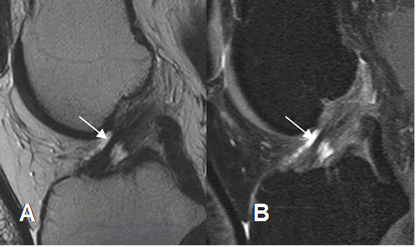

Fig 108. Ruptura parcial del LCA.

A: RM sagital en T2 y B: RM sagital en STIR. Adelgazamiento, con solución de continuidad en la mayoría de las fibras del LCA, por ruptura parcial.